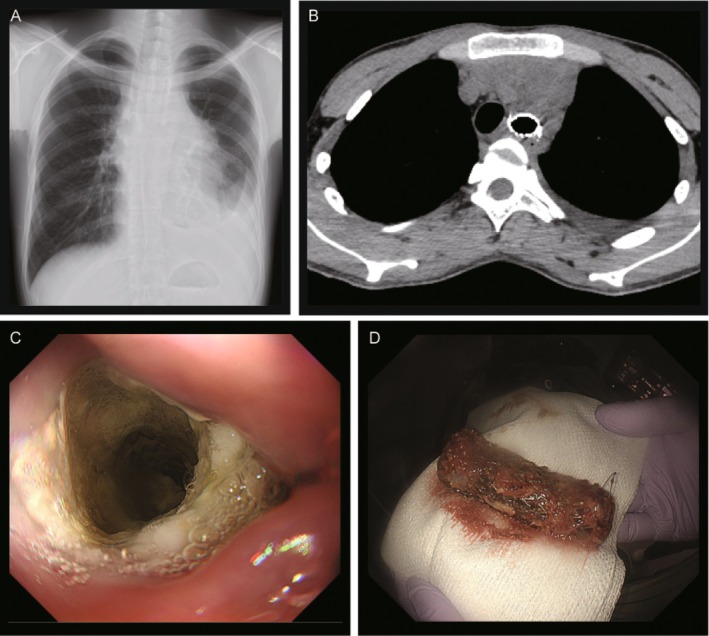

气道支架可以缓解恶性中央气道狭窄的症状,但存在移位的风险,这可能导致支架误食致死。一个22岁的男子接受混合式支架置入气管支气管狭窄的原因是一个未确诊的大纵隔肿块。放置后3周内,在初步诊断为b细胞淋巴瘤的化疗后,支架迁移并被摄入。内镜下成功取出支架。这是首次报道的混合型气管支架摄入病例。对预期肿瘤消退的患者进行早期监测是必要的。

Airway stents provide symptomatic relief in malignant central airway stenosis, but carry the risk of migration, which may result in potentially lethal stent ingestion. A 22-year-old man underwent hybrid stent placement for tracheobronchial stenosis caused by an undiagnosed large mediastinal mass. Within 3 weeks after placement, following initial chemotherapy for provisionally diagnosed B-cell lymphoma, the stent migrated and was ingested. The stent was successfully retrieved endoscopically. This is the first reported case of hybrid tracheal stent ingestion. Early surveillance is warranted in patients with anticipated tumour regression.